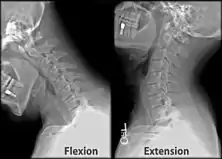

X-ray of cervical spine in flexion and extension